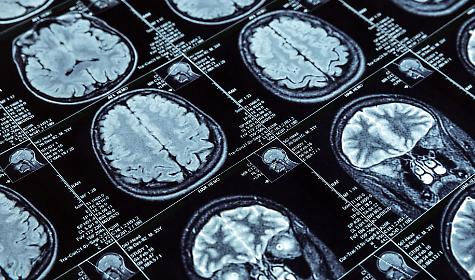

L’ictus è una grave alterazione del flusso sanguigno cerebrale che provoca la perdita improvvisa di funzioni neurologiche. Accade quando un’area del cervello non riceve più l’ossigeno necessario a causa di un’interruzione del sangue che la dovrebbe raggiungere. È una delle principali cause di morte e disabilità nel mondo e rappresenta un’emergenza tempo-dipendente: intervenire rapidamente può salvare vite e limitare danni permanenti.

Esistono due forme principali. Il ictus ischemico (circa l’80% dei casi) è causato da un trombo o un embolo che ostruisce un’arteria cerebrale, bloccando il flusso di sangue. L’ictus emorragico, invece, si verifica quando un vaso sanguigno si rompe, causando un’emorragia nel cervello. In entrambi i casi, le cellule cerebrali iniziano a soffrire già dopo pochi minuti.